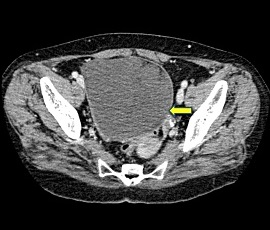

急性腹症にて救急受診。腹部超音波検査にて骨盤内に子宮、膀胱を圧排する約15cm大の辺縁が円滑な単房性腫瘤(矢印)を認め、精査の結果、卵巣腫瘍(矢印)と診断。手術を施行した。病理結果は、成熟嚢胞性奇形腫であった。

CT画像